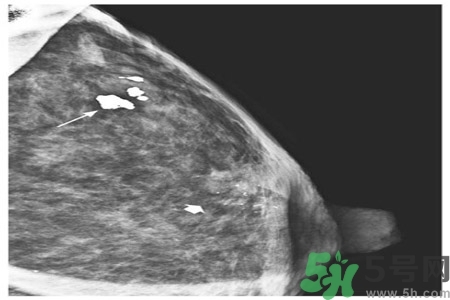

早期乳腺癌唯一的X線征象

成簇樣微小鈣化常是早期乳腺癌唯一的X線征象。根據(jù)微小鈣化形態(tài)、大小、數(shù)量和密集度等表現(xiàn)可反映病變性質(zhì)和范圍。微小鈣化點(diǎn)可位于腫塊內(nèi)或周圍,總數(shù)目6~15枚,密度不均,大小不等。

乳腺X線檢查可提高隱匿癌、微小癌(直徑小于10mm)和早期癌的診斷率。直徑小于10mm腫塊定性困難,但細(xì)沙型鈣化常是惡性病變的警報(bào);若同時(shí)出現(xiàn)周圍結(jié)構(gòu)紊亂,雙側(cè)不對(duì)稱,血管影增粗等征象則惡性病變可能性更大。